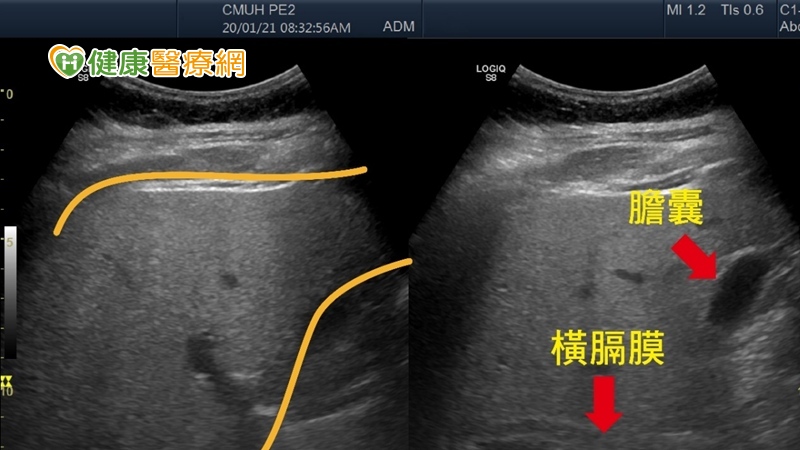

▲2條黃色線內是肝臟的範圍,肝臟因堆積較多脂肪,導致超音波下肝臟是白花花一片,箭頭處為膽囊與橫膈邊界變得模糊,是重度脂肪肝的影像表現。(圖/中國醫藥大學附設醫院提供)